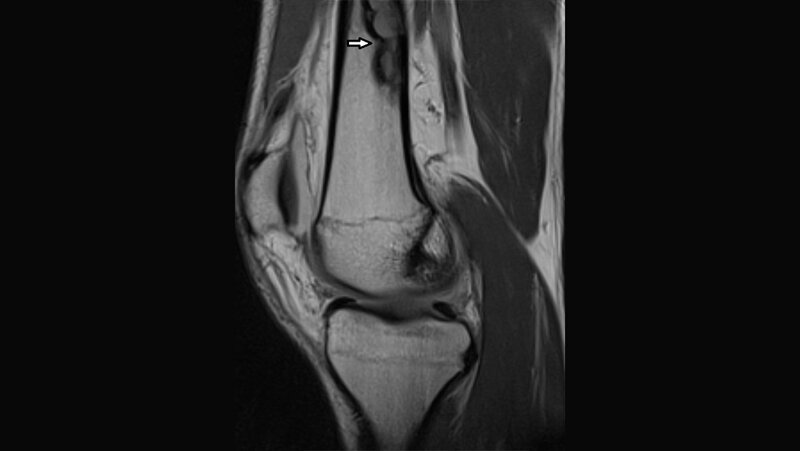

Das nicht ossifizierende Fibrom ist eine tumorähnliche und nicht neoplastische Veränderung des Knochens. Die meisten der Läsionen benötigen keine Therapie. Die meisten NOF kommen in den Metaphysen der langen Röhrenknochen der unteren Extremitäten vor.

The non-ossifying fibroma is a tumor-like lesion and defined as non-neoplastic bone lesion. Some lesions do not need treatment. The most cases of NOF occur in the metaphyses of the long tubular bones of the lower extremities.